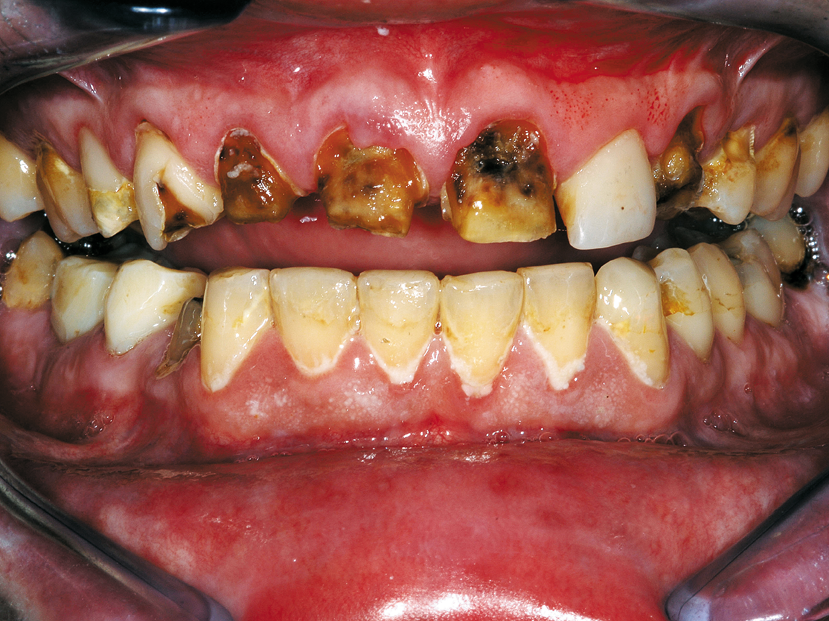

This clinical case demonstrates the use of CORE-FLO DC LITE with Bisco’s dual-cured UNIVERSAL PRIMER for post and core build-ups. The patient presented with advanced decay in multiple teeth. He was a relatively healthy 30-year-old male with a history of drug and alcohol abuse. He had recently completed a substance abuse rehabilitation program and wanted to finish his dental treatment.

He stopped his prior dental treatment while still in his temporary restorations. He eventually lost the temporaries and went without for several years. As a result he was left with extensive decay in the previously prepared anterior teeth (Figs. 1, 3).

He also had numerous areas of new decay in most of his remaining teeth, requiring a full mouth reconstruction. Our treatment plan was a 24 tooth reconstruction (missing first bicuspids) with root canal treatment for teeth #7-11 with fiber post build-ups using CORE-FLO DC LITE.